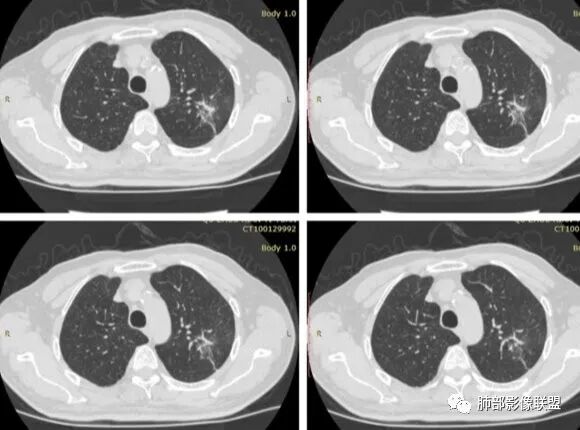

边缘收缩均匀、U型凹陷、内有小点状钙化、桃尖征

支持炎性放前面、

不放心的是部分区域膨隆

结      核

本例小结

1、患者老年男性,无明显临床症状。

2、病灶位于左肺上叶尖后段,符合肺结核好发部位。

3、病灶密度不均,可见钙化点,未显示空洞或液化。边缘收缩,U型凹陷、桃尖征、细长毛刺以及较长棘状突起。宽基底与胸膜相连,邻近胸膜广泛性增厚(未见栽赃侵入)。可见卫星病灶,周围的磨玻璃影比较松散,炎性病变征象多,符合结核的CT表现。

4、部分区域膨隆,未见支气管截断,肺门纵隔未见肿大淋巴结等,恶性征象少。

5、结合其无临床症状、病灶形态、病灶位置及发病率,结核居多,最后诊断在大家意料之中。